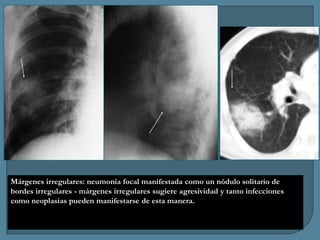

Márgenes irregulares: neumonia focal manifestada como un nódulo solitario de

bordes irregulares - márgenes irregulares sugiere agresividad y tanto infecciones

como neoplasias pueden manifestarse de esta manera.